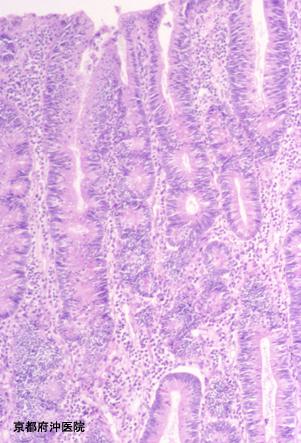

症例提示(所在地,施設名等): 京都府・ 沖医院

症例登録日 2002/07/08

画像ID:3542

部位(臓器別)大腸/盲腸

検査方法ミクロ

腫瘍の肉眼分類0型(表在型)/I型(Ip)

病変の最大径(ミリ)40以上